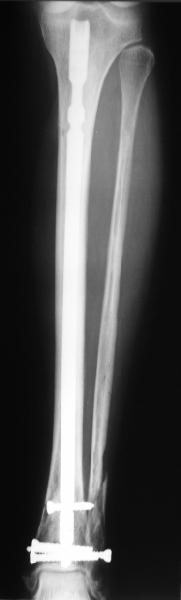

A typical case is attached, also an image with intra-op reduction obtained by a small wire distractor, in the moment of insertion a Poller wire in AP direction. Fixation by a SIGN nail. Despite the fibula was not fixed healing was obtained with the unchanged alignment.

I am just trying to illustrate that prevention of 1)tibial valgus and 2)loss of reduction can be provided without fibular plating. Small changes of conventional nailing techniques allow to maintain reduction of the tibia reliably without adjunctive fibular stabilization.

In delayed cases acute length restoration performed only in the tibia may leave the fibula shortened thus change the mortise. So it is reasonable to restore length of both bones simultaneously by distractor and fix the fibula not with open reduction and plating but just by a single perQ screw. Example attached.